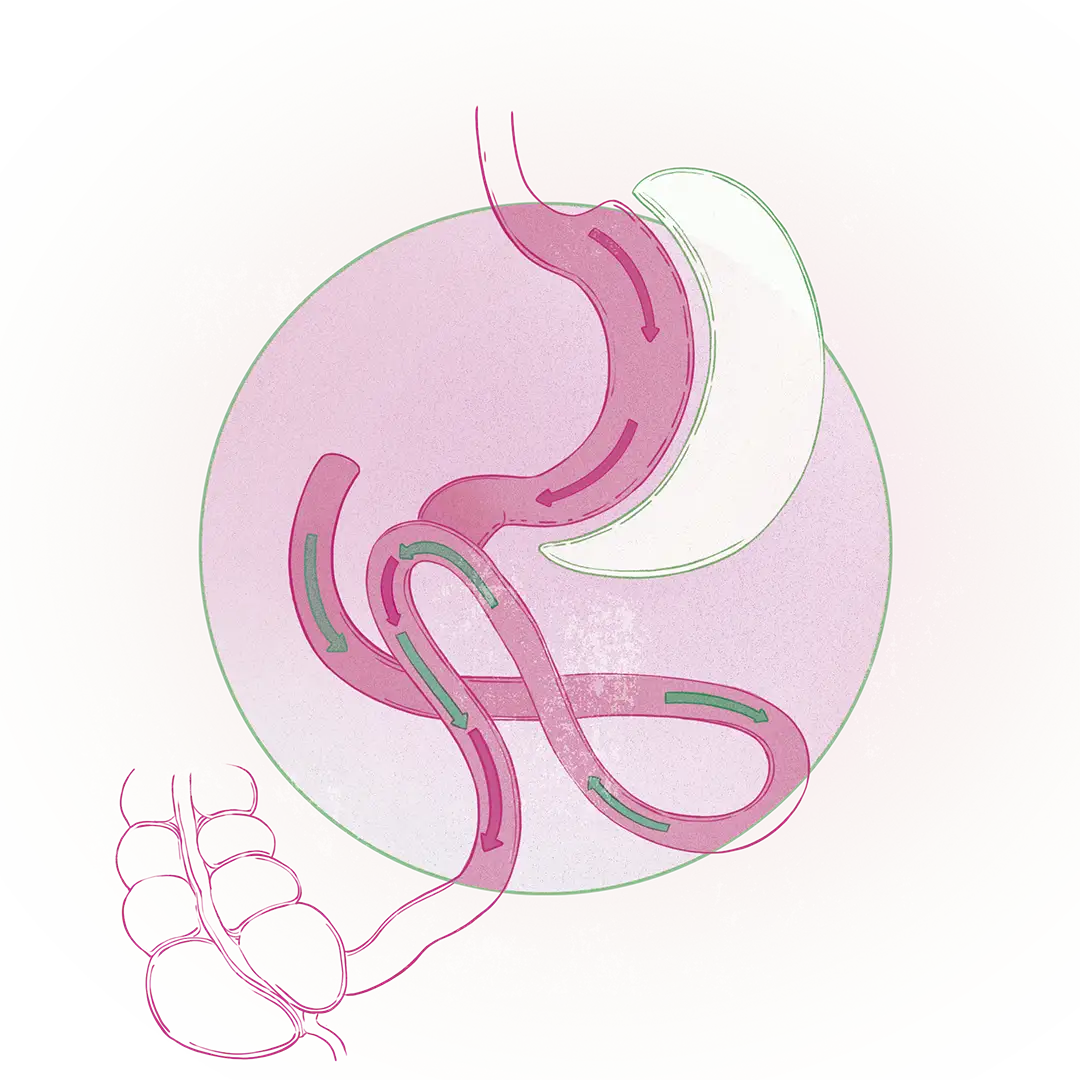

- Cirugía bariátrica mixta: Incluye la acción restrictiva de la manga gástrica y añade el factor de malabsorción, es decir, impide el paso de comida por una porción del intestino delgado, así que la persona come menos y su organismo no absorbe todo lo que come. La cirugía malabsortiva más importante es el bypass gástrico.

- Cirugía bariátrica malabsortiva: Predomina la malabsorción sobre la restricción del alimento. La cirugía más importante en este campo es el bypass SADIS, que es una combinación del bypass gástrico y la manga gástrica.

El tipo de cirugía para cada paciente se escoge según la edad, la cronología de la obesidad, las enfermedades asociadas (como la diabetes o la hipertensión) y el grado de obesidad diagnosticado, que se basa en el índice de masa corporal (IMC). “Si la persona tiene menor grado de obesidad y pocas enfermedades asociadas, lo ideal será la manga gástrica; sin embargo, cada caso se evalúa individualmente", agrega Ospina.